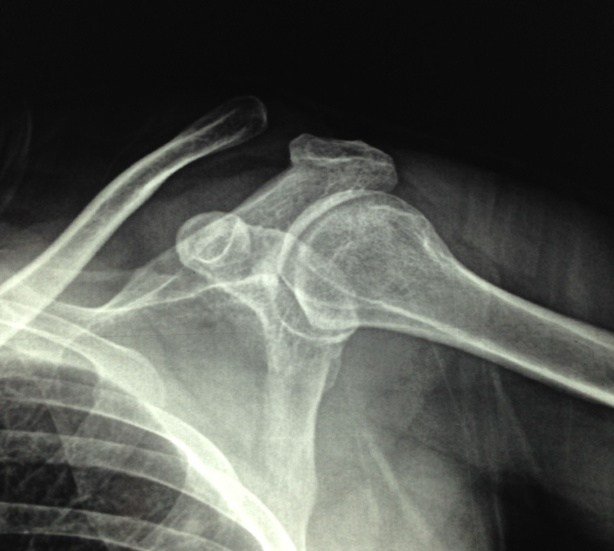

Chẩn đoán cận lâm sàng – hình ảnh trật khớp cùng đòn

- X quang trật khớp cùng đòn: Chụp X-quang khớp vai trước – sau, chụp nghiêng tư thế hình chữ Y hoặc chụp nghiêng tiếp tuyến với khớp cùng đòn 10 – 15° sẽ giúp chẩn đoán xác định và phân loại trật khớp cùng đòn. Trường hợp trên lâm sàng nghi ngờ trật khớp cùng đòn nhưng hình ảnh trật khớp cùng đòn Xquang thông thường không thấy tổn thương thì sẽ phải chụp lại bằng cách yêu cầu người bệnh cầm vật nặng trên tay để kiểm tra khớp cùng đòn khi không cầm vật nặng, đồng thời so sánh với bên đối diện. Đặc điểm trật khớp cùng đòn trên X-quang: Phù nề phần mềm, khớp cùng đòn bị rộng, bất đối xứng so với bên đối diện.